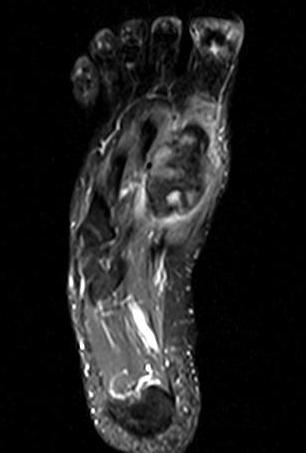

Osteoid osteoma

Especially common in hindfoot

Difficult to diagnose on x-ray - CT / MRI / bone scan

CT guided RF ablation